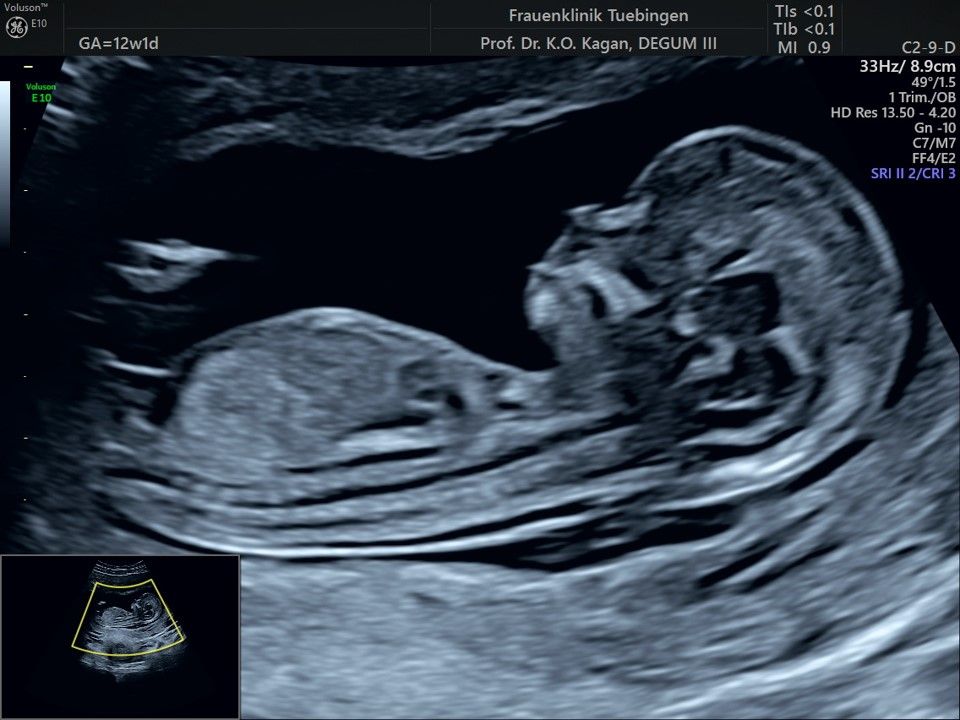

Im Rahmen des Ersttrimester-Screenings untersuchen wir die Organe des Feten mittels Ultraschall. Dabei machen wir auch gerne ein Bild für Sie.

Obwohl der Fet zu diesem Zeitpunkt erst zwischen 5 und 8cm groß ist, lassen sich bereits etwa die Hälfte aller schwerwiegenden Fehlbildungen erkennen bzw. ausschließen. Sollten wir eine Auffälligkeit sehen, werden wir mit Ihnen den Befund und das weitere Vorgehen ausführlich besprechen.

Fetale Anatomie